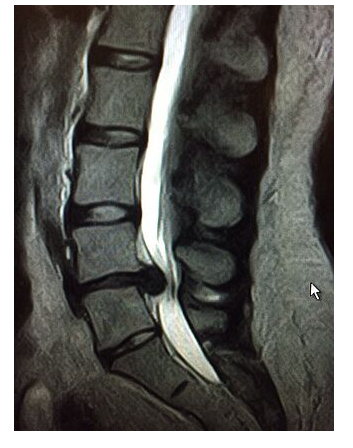

Так как на обычной рентгенограмме грыжа межпозвонкового диска не видна, поэтому дальнейшая дифференциация должна быть достигнута с помощью компьютерной томографии или магнитно-резонансной томографии (МРТ), а также ЭНМГ - электронейромиографии конечностей.

Особенно важно выполнять МРТ того или иного отдела позвоночника если болевой синдром сохраняется более 2-х месяцев. Нередко под маской дегенеративного процесса может скрываться онкологическое заболевание, а пациенту ошибочно назначают в течение этого времени, например физиотерапевтические процедуры, активизирующие онкологический процесс.

МРТ позвоночника позволяет точно определить наличие, локализацию, направленность и степень воздействия грыжи позвоночного диска на нервные корешки. В некоторых случаях показано контрастирование позвоночного канала в сочетании с компьютерной томографией.